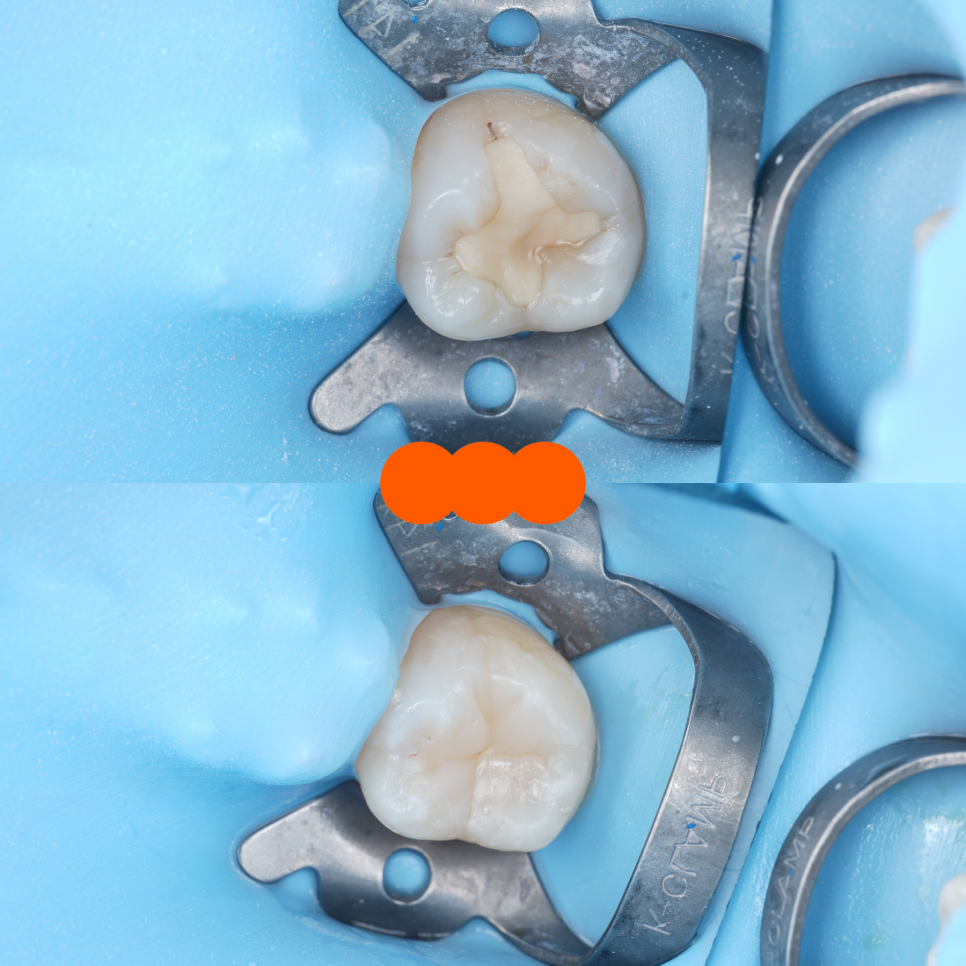

어금니도 충치 제거 후 자연스레 쌓아 올렸어요.

촬영일 : 250909 / 250909

#37 완료 / 촬영일 : 251021

그 뒤로 레진을 이용해 말끔하게 채워드렸죠.